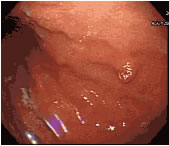

위 점막의 표면 위로 솟아 올라온 혹을 말하는 것입니다. 위용종, 위폴립, 위물혹, 양성 위종양 등으로 불리워지며 선종성 용종이라고 불리기도 합니다. 위용종은 대개 양성 질환이며, 특별한 경우를 제외하면 암으로 진행하지 않습니다.

염증성 용종, 과증식성 용종 및 선종성 용종으로 분류될 수 있습니다.